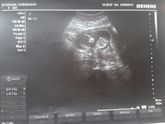

Всем привет!) Была сегодня на скрининге. Всё хорошо. 12-13 недель. Всё на месте. Пошла к врачу, её не было, медсестра дала направление на кровь и обменку дали на руки. Вот так. Пол даже не предположили..((

Фотография